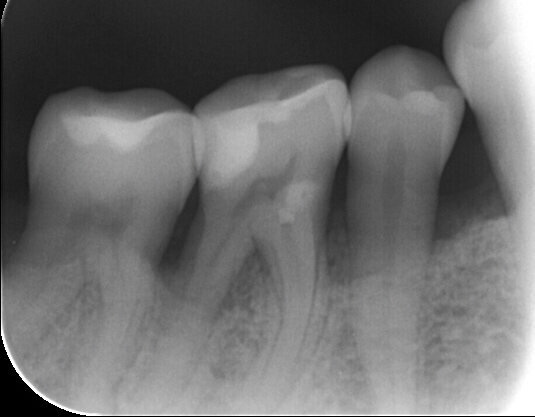

Viene perciò effettuata una visita parodontale completa con compilazione della cartella parodontale, set fotografico e raccolta dello status radiografico. Il profilo di rischio parodontale della paziente, stilato in base ai criteri del Periodontal Risk Assessment1 risulta essere di tipo “alto”. Vista la perdita di attacco clinico (CAL) nel sito con maggiore interessamento (≥5 mm), la perdita ossea valutata radiograficamente (RBL), la progressione della malattia (valutata “moderata”), la diagnosi è di Parodontite Generalizzata di Stadio IV e Grado B2. Osservando la cartella parodontale si può notare una maggiore progressione della malattia nei sestanti III, IV e VI con sondaggi superiori ai 6 mm a carico degli elementi 2.4, 3.6, 3.7, 4.4, 4.5, 4.6. e 4.7, BOP (Bleeding on Probing) positivo e SOP (Suppuration on Probing) positivo nei siti 2.4. e 4.6.

Fig. 3 - Status radiografico al T0.

Fig. 5 - Rx peri-apicale dell’elemento 4.6: difetto intra-osseo e abbondante presenza di tartaro.